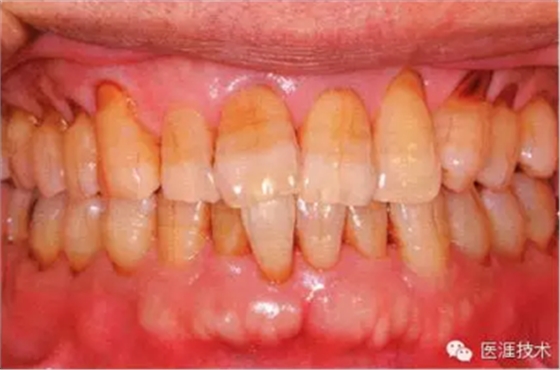

55歲牙周炎男性的臨床照片

55歲男性抽煙患者(1天20支、抽煙35年)。菌斑控制得不好。通過牙周探診,全頜有4~9mm的牙周袋,有1~3度的根分叉部病變。通過X光片觀察,上頜前牙中度牙槽骨吸收,其他地方有中度牙槽骨吸收。受吸煙影響,牙齦纖維性肥厚,呈紅黑色。牙齦幾乎沒有浮腫和發(fā)紅,所以這個病例是從外觀上無法預測病癥嚴重程度的病例。